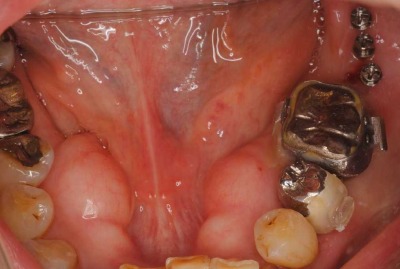

治療では、左下の奥歯に3本の矯正用インプラントを入れました。

拡大した写真です。

レントゲンで見ると分かりますが、結構小さいインプラントです。

このインプラントを支えにして、奥歯を元の後側の位置まで引っ張りました。